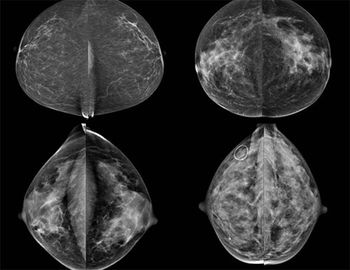

CHICAGO-Challenging breast density as a strong risk factor for cancer.

CHICAGO-The effect of expanded Medicaid to allow screening access on rates of breast cancer screening.